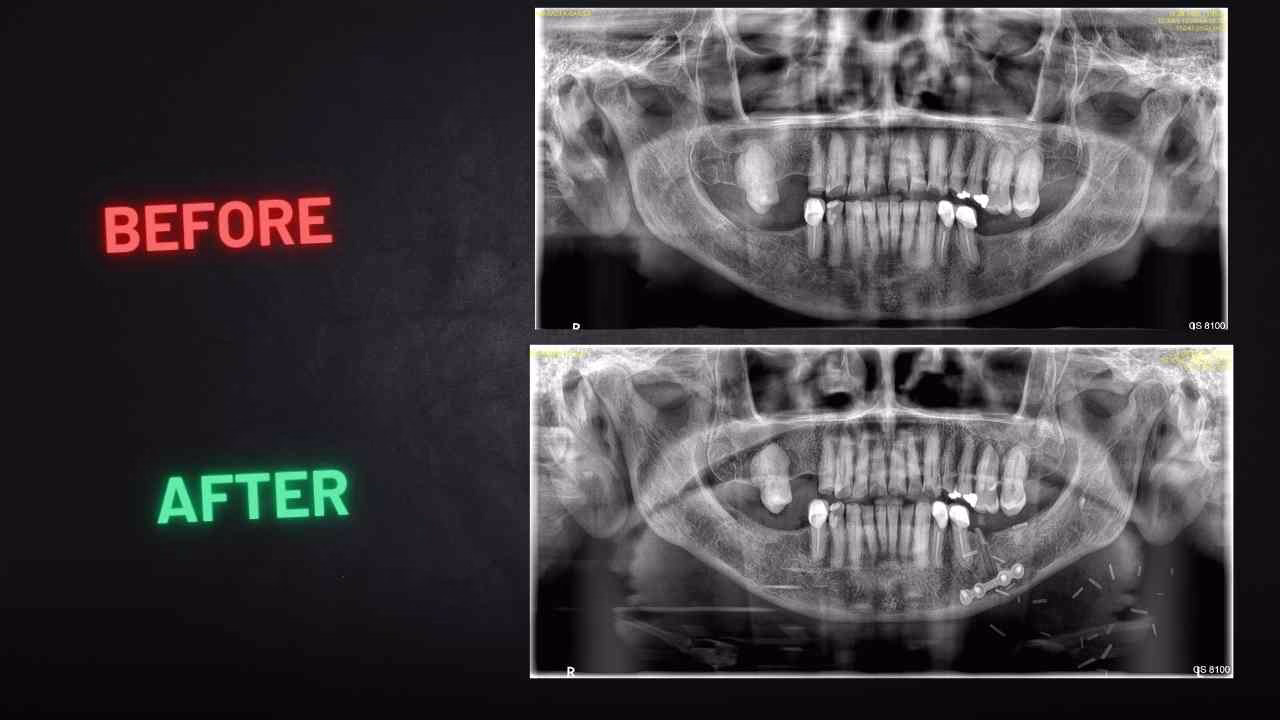

Precision Tumor Resection: We performed a mandibulotomy to access and completely remove the tumor from the posterior tongue.

Ensuring Complete Removal: Intraoperative frozen section biopsies confirmed negative margins, meaning all cancer cells were eliminated.